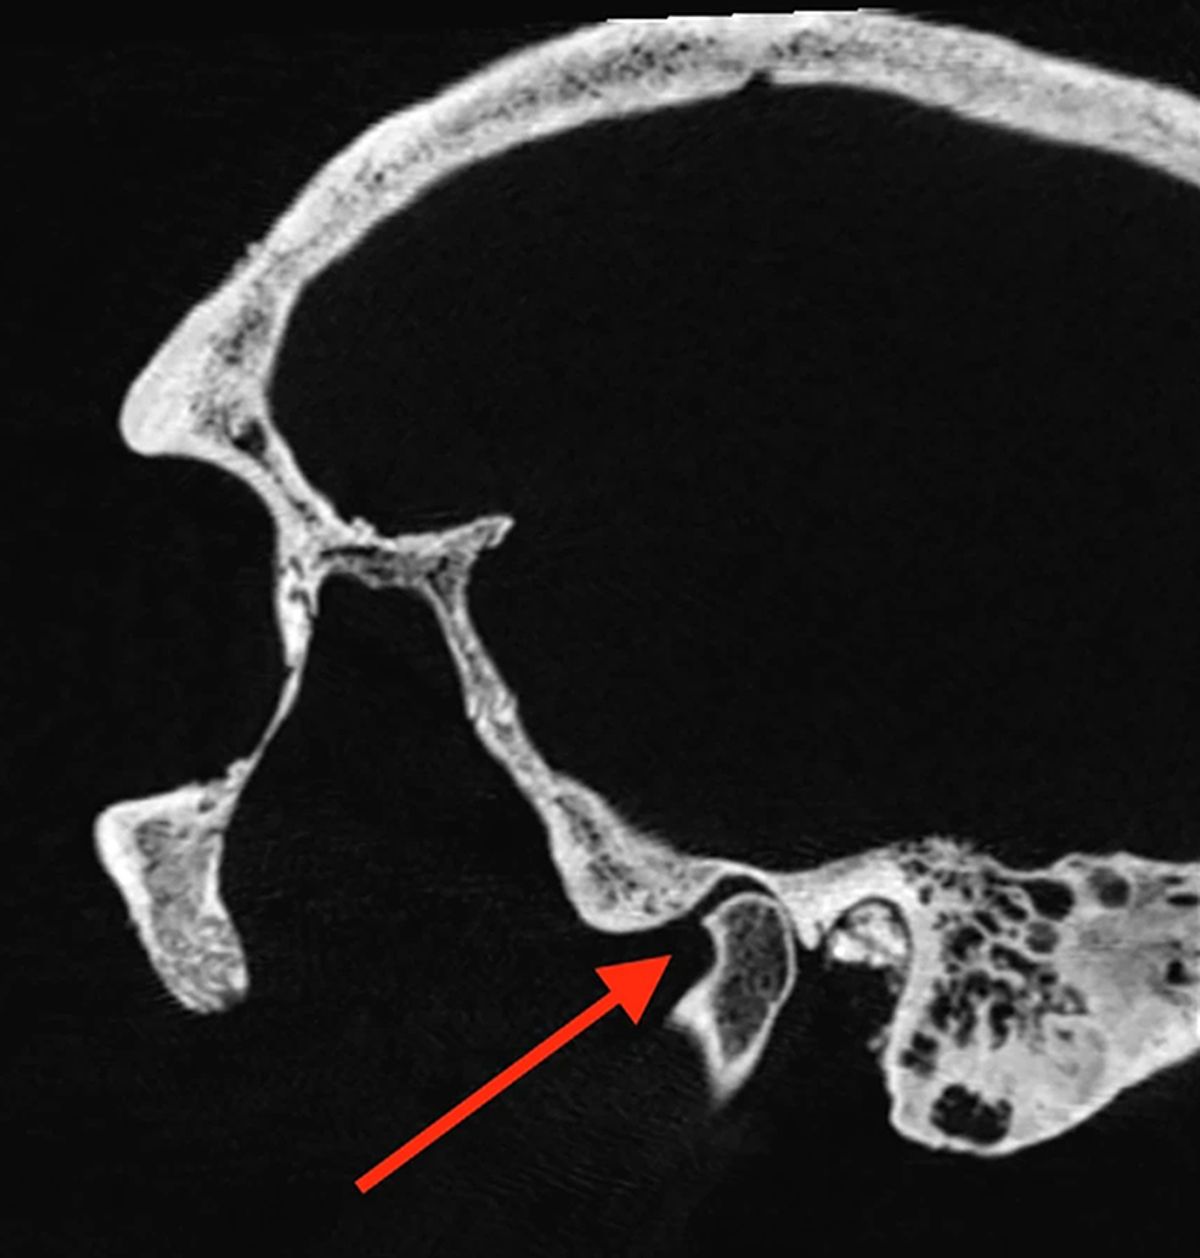

Mediante tomografías computarizadas —un tipo preciso de rayos X en tres dimensiones— el equipo detectó daños tanto en la superficie como en el interior de los cráneos. Este método permitió mapear las lesiones y relacionarlas con sus probables causas, demostrando el enorme valor informativo que pueden proporcionar estos escaneos en restos arqueológicos.

Según los investigadores, aplicar esta técnica de tomografía computarizada a otros restos antiguos podría revelar toda clase de nuevos descubrimientos que pasarían desapercibidos con una inspección visual normal, y sin causar daños innecesarios a las muestras.